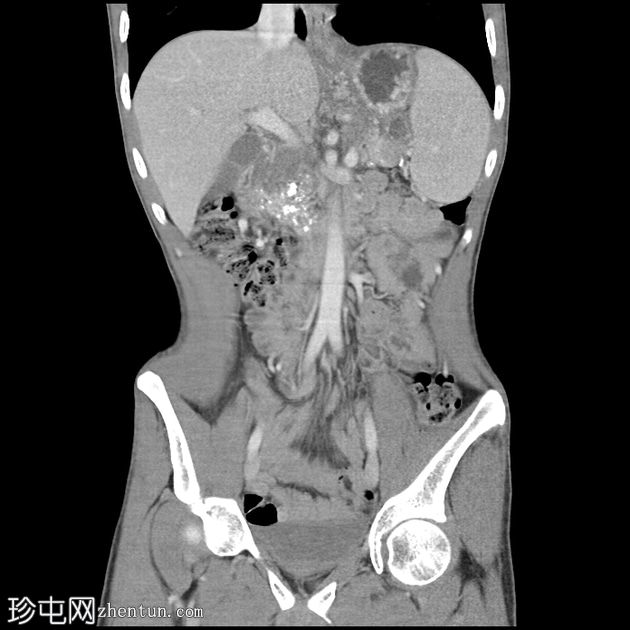

冠状位增强扫描

门静脉期

胰腺肿大。胰头、胰颈和胰体未见强化,边界不清且不规则。主胰管扩张,管内可见钙化。

胰腺实质内弥漫散在分布着大量钙化灶。

胰尾可见部分强化区域。

胰尾部钙化性假性囊肿。

影像学表现提示慢性钙化性胰腺炎伴胰尾部钙化性假性囊肿。

弥漫性实质及导管钙化是慢性钙化性胰腺炎的典型特征。

胰头及胰体无强化、形态不规则提示纤维化程度较重。

钙化性假性囊肿是一种慢性并发症,可通过囊壁钙化与肿瘤相鉴别。

CT是评估实质缺损、导管改变、钙化及假性囊肿的首选影像学检查方法。